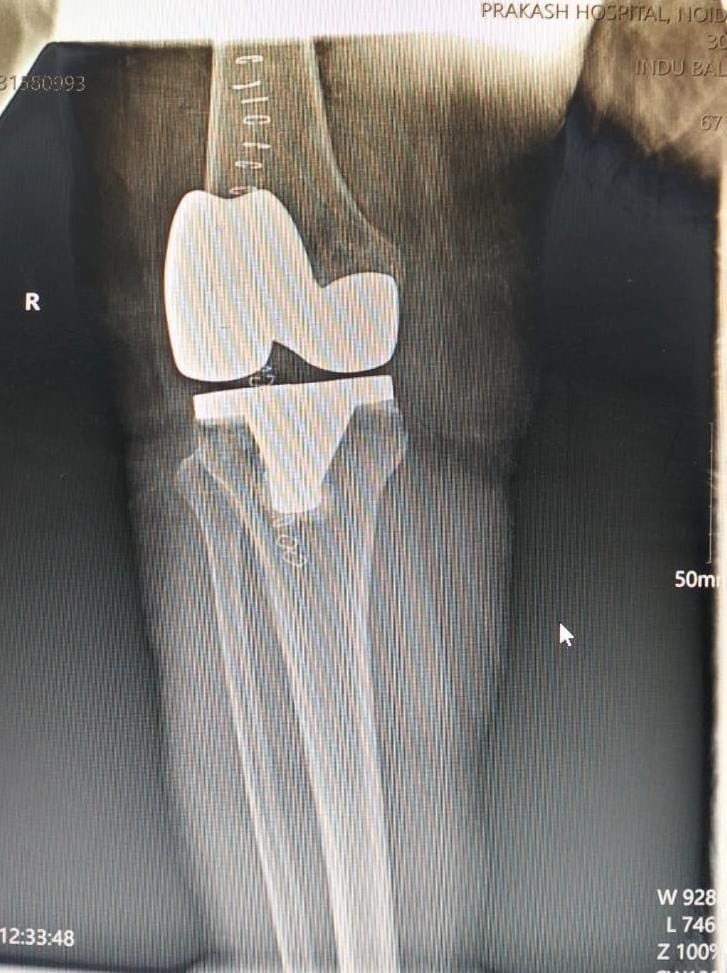

Knee replacement surgery is a procedure where damaged parts of the knee joint are replaced with artificial components to relieve pain and restore function.